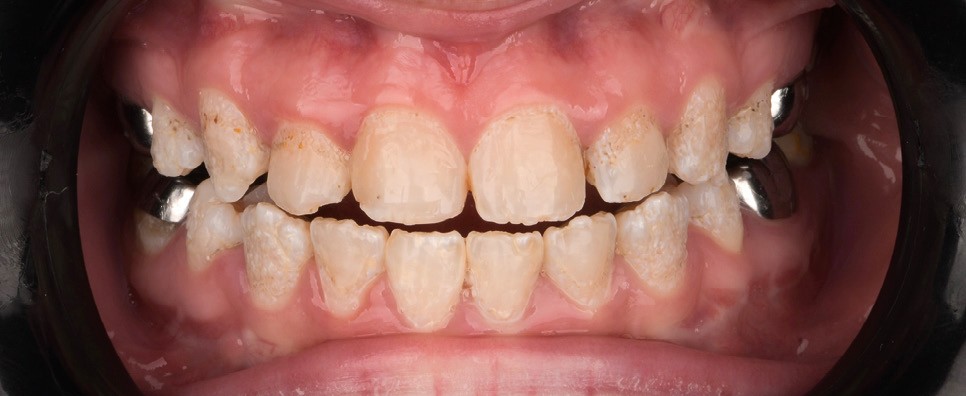

Lors de l’arrivée de la patiente, un examen clinique au fauteuil est effectué, complété par une empreinte numérique permettant l’enregistrement précis des arcades dentaires et de l’occlusion existante. Cet examen initial met en évidence une pathologie de type amélogenèse imparfaite. On note également la présence de couronnes métalliques au niveau des premières molaires, ainsi que de multiples restaurations, notamment au niveau des dernières molaires (fig. 1 à 4).

La première étape décisionnelle repose sur une analyse esthétique du visage et du sourire, réalisée à l’aide du logiciel SmileCloud. Cette analyse permet d’évaluer les proportions dentaires, la ligne du sourire et les rapports dento-labiaux. Elle confirme que le traitement vise à la fois la protection d’un émail de mauvaise qualité et l’amélioration de l’esthétique globale, avec notamment une optimisation des proportions dentaires (fig. 5 et 6).